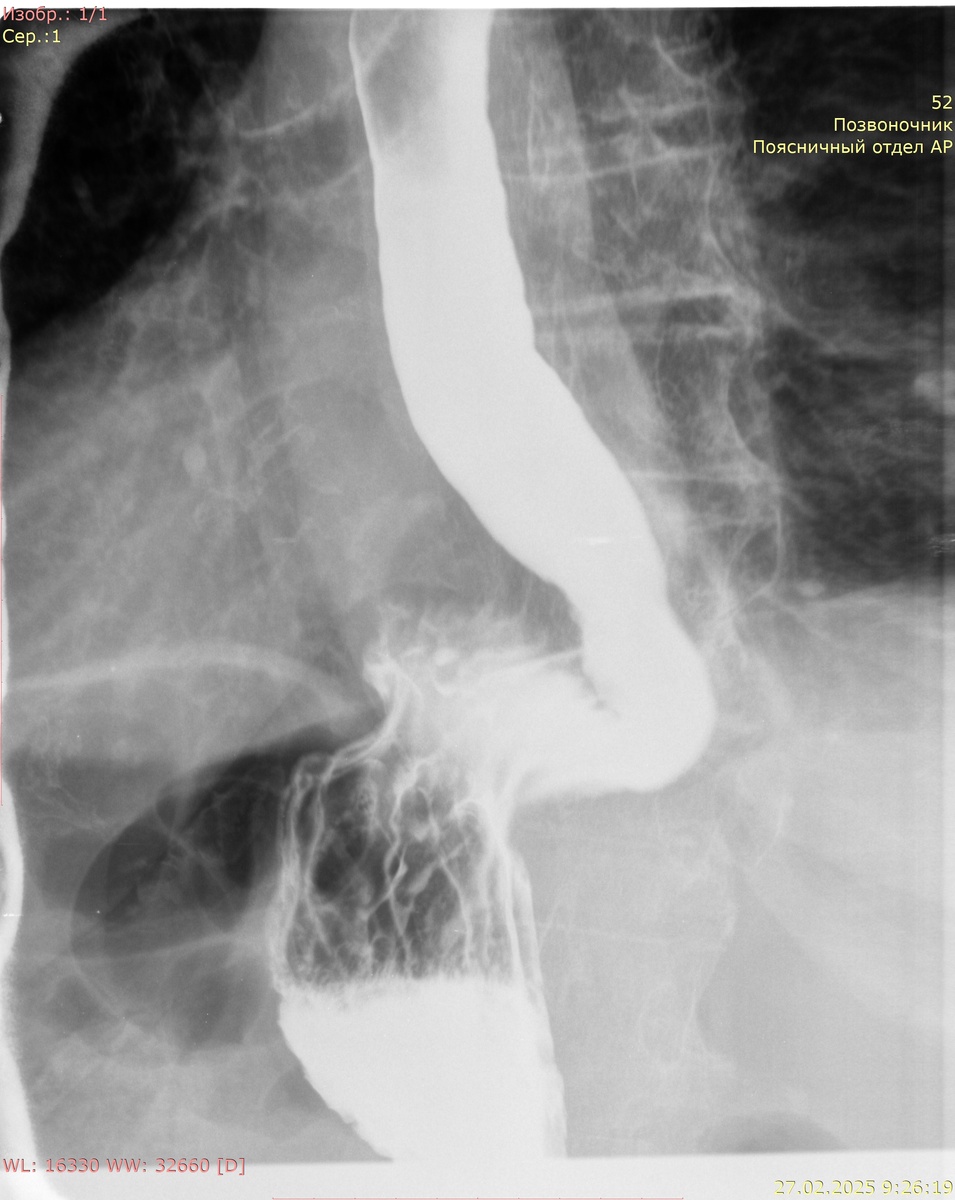

Рентгенография желудка с сульфатом Ва:

Кардиальный жом функционирует. Желудок не деформирован, объем обычный, смещаемость не нарушена. Контуры желудка ровные, отвесные, участков деформации не выявлено. Рельеф слизистой не изменен, складки не утолщены. Контраст своевременно поступает в ДПК. В положении стоя и лежа без натуживания определяется пролабирование кардиальных складок выше диафрагмы размерами 99 мм х 80 мм.

Заключение: картина фиксированной грыжи пищеводного отверстия диафрагмы 4 ст.